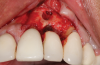

In this case, a dental implant that had been placed 10 years prior was functional, stable, and esthetically acceptable to the patient. However, a significant fistula was present on the facial-apical aspect of the ridge in the maxillary lateral incisor area. This area was painfully sensitive to touch and demonstrated purulence when squeezed. To evaluate the lesion, first, a conventional digital radiograph was acquired, which revealed an apical radiolucency at the apex of the implant (Figure 1). Further analysis using cone-beam computed tomography (CBCT) demonstrated a fistula from that site to the oral environment (Figure 2). Treatment options were discussed, including removal of the implant, followed by grafting, a healing period, and replacement of the implant and implant-retained crown. If this option was selected, a transitional appliance would need to be created. Another option was to attempt to salvage the implant and implant crown by treating the infection and grafting the site to create a new boney wall and eliminate the fistula. Ultimately, the patient accepted this option to attempt to salvage the fixture and crown.

(1.) Preoperative radiographic evaluation demonstrating a large radiolucency at the apical third of the body of an implant fixture replacing the patient’s maxillary left lateral incisor. The implant was stable, and the prosthesis was deemed esthetically acceptable by the patient.

Figure 1